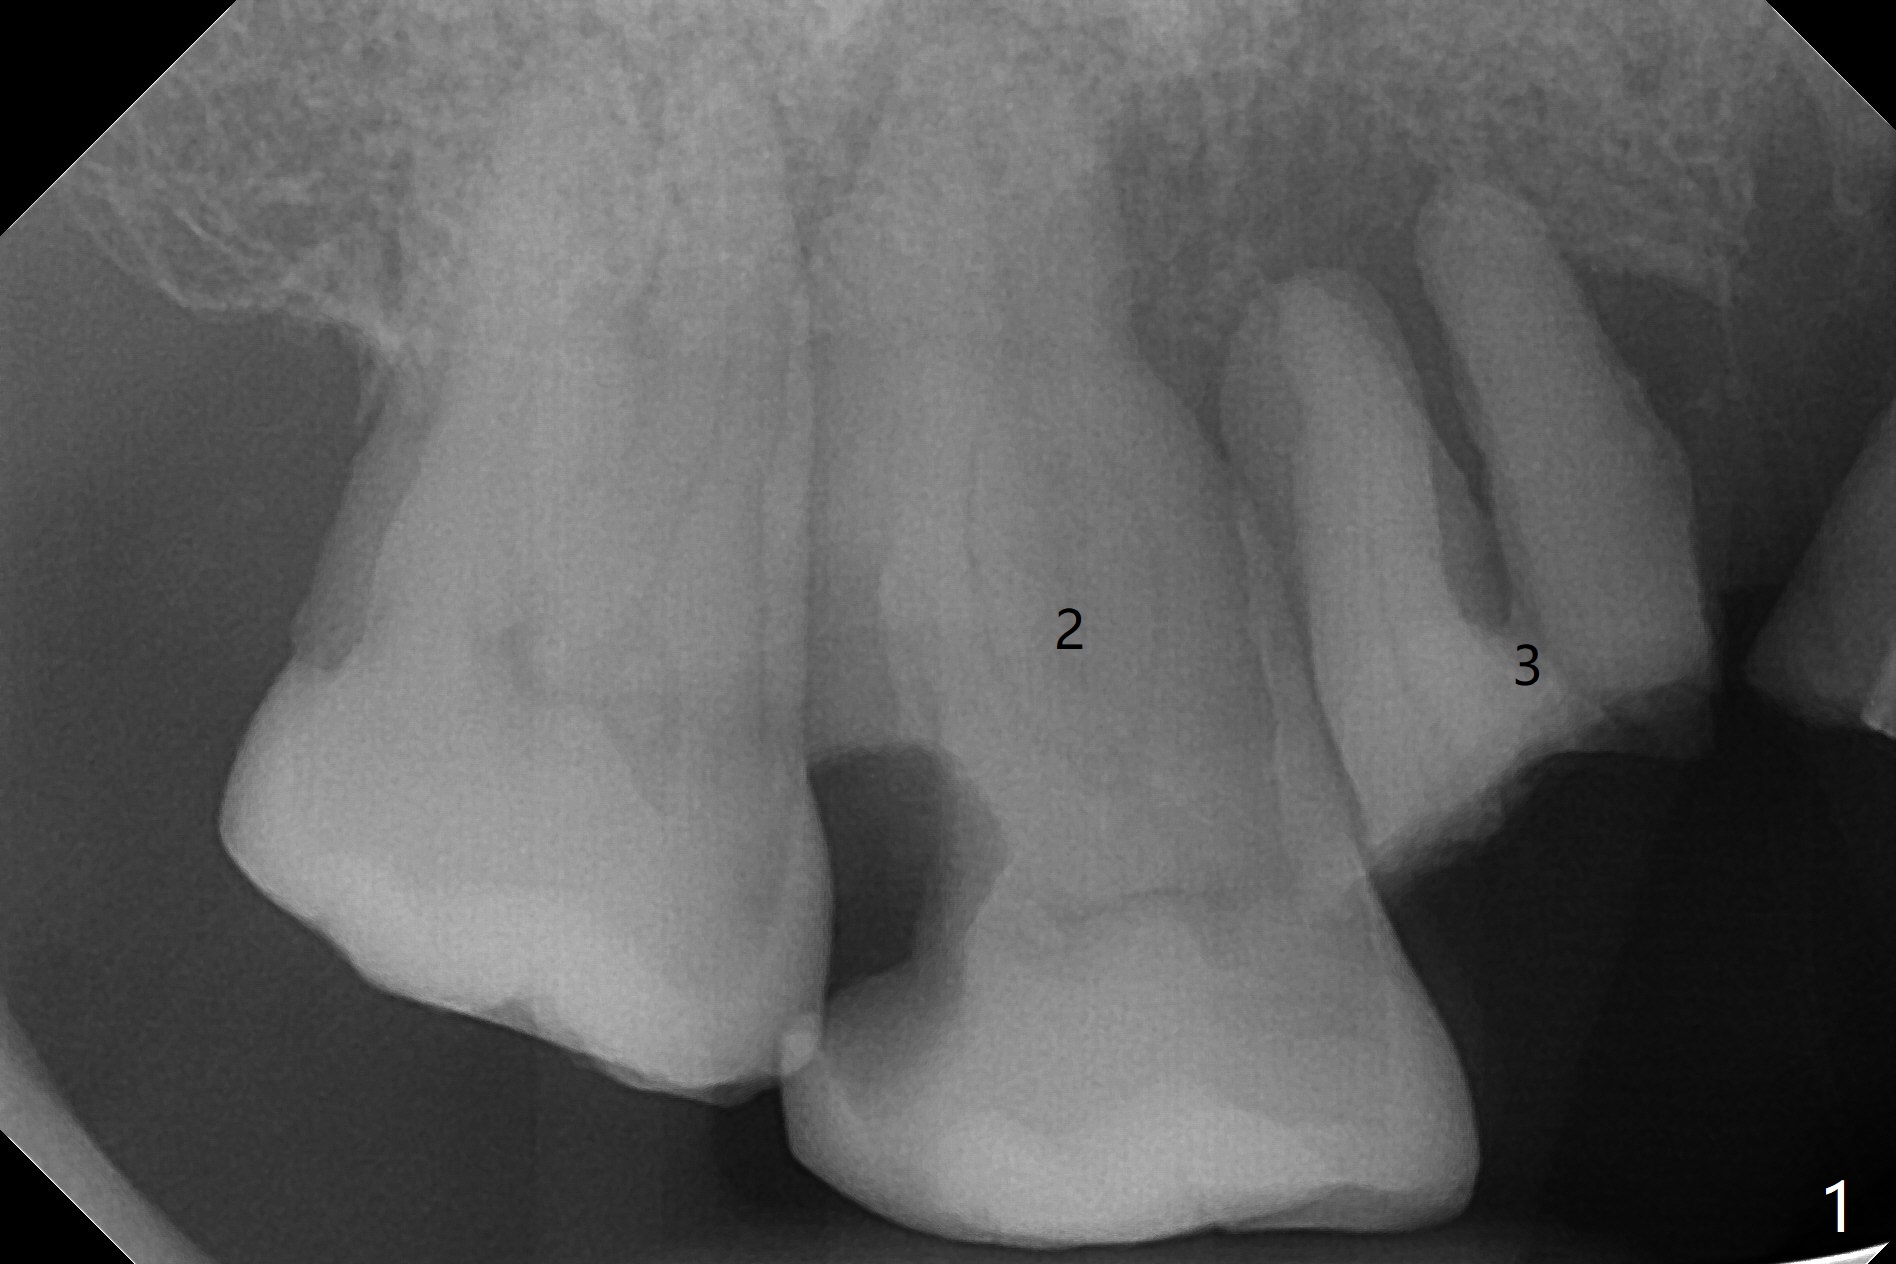

A 70-year-old man has poor dentition, needing extraction for dentures (including #2 and 3 in Fig.1). To save the abutment tooth #1 (with severe bone loss) for RPD and to stop hemorrhage, allograft and Osteogen Plug are placed at #2 and Collagen Plug at #3. Five-O PGA sutures remain in place 9 days postop (Fig.3).